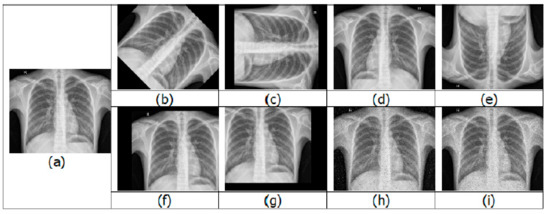

Having a large training dataset image in DL helps in improving the training accuracy. When compared with a strong algorithm with modest data, a weak algorithm on large-scale data can be more accurate. The presence of imbalanced classes is another obstacle that is encountered. The resulting model would be biased when the number of samples belonging to a particular class is larger than the other class during binary classification training. For the optimal performance of DL algorithms, the number of samples should be equal or balanced in each class. Image augmentation is a technique to increase the training dataset by creating variations of the original images, without obtaining new images. The variations are achieved by various processing methods such as flips, rotations, zooms, adding noise, and translations [11]. A few examples of augmented images are shown in Figure 2.

Overfitting is also prevented during data augmentation, where the network tries to learn a very high variance function. Data augmentation addresses it by introducing the model with more diverse data, which decreases variance and improves the generalization of the model. Some of the disadvantages of data augmentation are its inability to overcome all biases in a small dataset [12], transformation computing costs, additional training time, and memory costs.

Figure 2. Examples of image augmentation: (a) original; (b) 45° rotation; (c) 90° rotation; (d) horizontal flip; (e) vertical flip; (f) positive x and y translation; (g) negative x and y translation; (h) salt-and-pepper noise; (i) speckle noise.